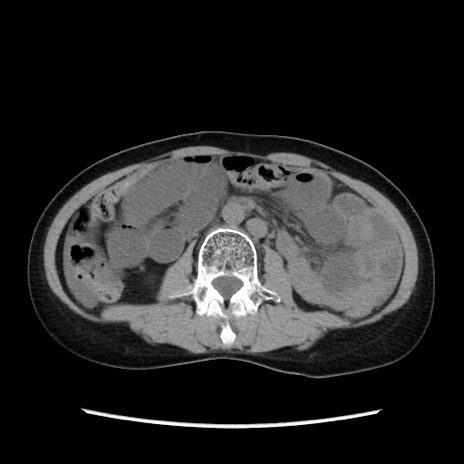

冠状断像

【症例】40歳代 女性

【主訴】上腹部痛、嘔気・嘔吐

【現病歴】約9時間前頃から急に上腹部痛、嘔気、嘔吐が出現。改善しないため救急要請。

【既往歴】子宮頚癌(広汎子宮全摘術、放射線療法)、腸閉塞

【身体所見】腹部:平坦、軟、腸雑音亢進、上腹部を中心に腹部全体に圧痛あり。

【データ】WBC 8400、CRP 0.03